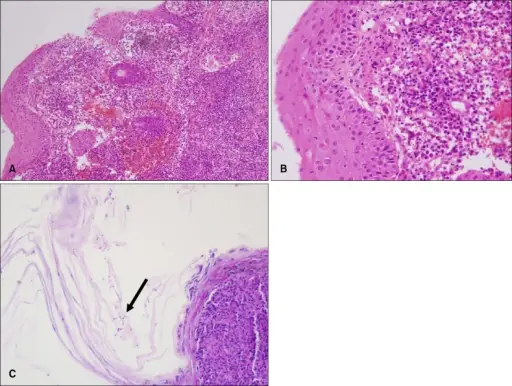

Squamous Cell Carcinoma

Squamous cell carcinoma (SCC) is the second most frequently diagnosed cancer worldwide.

Squamous cell carcinoma (SCC) accounts for about 30% of cancer cases in men and 20% of cases in women.

Two important risk factors for squamous cell carcinoma (SCC) are alcohol and tobacco use.

Invasive squamous cell carcinoma (SCC) may develop from oral leukoplakias and erythroplakias, which are precancerous diseases.

Although they can appear anywhere in the oral cavity epithelium, these lesions typically grow at the mouth’s floor.

Histologically, squamous cell carcinoma (SCC) is identified by alterations in the stratified squamous epithelial layers, such as invasion into the underlying connective tissue and hyperkeratosis, parakeratosis, acanthosis, keratin pearls, and dysplasia.